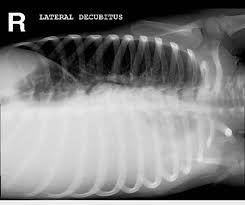

X-ray Chest Decubitus Right

Are you looking for an accurate and affordable X-Ray Chest Decubitus Right? Medifyhome offers high-quality imaging services through NABL and NABH-accredited diagnostic centers, ensuring reliable results. This particular X-ray takes images in a lateral decubitus position, which aids in the detection of fluid accumulation, pneumothorax, and other chest abnormalities. We prioritize patient comfort, safety, and quick report delivery by employing cutting-edge equipment and skilled radiologists. Schedule your X-ray today by calling +919100907036 / +919100907622, and Medifyhome will provide the best diagnostic treatment!

- An X-ray Chest Decubitus Right is a specialized imaging procedure applied to examine conditions like pleural effusion, pneumothorax, or other abnormalities by taking images. The patient lies on his or her right side at the same time. The patient rests on his or her right side at the same time. The position enables the detection of fluid flow, air trapping, and lung collapse, which cannot be detected on a routine chest X-ray.

An X-ray Chest Decubitus Right Scan is a chest X-ray taken with the patient lying on their right side. This position helps detect small pleural effusions, pneumothorax, or fluid movement in the lungs that might not be visible on standard chest X-rays.

An X-ray Chest Decubitus Right can detect small pleural effusions, pneumothorax (air in the chest cavity), lung fluid shifts, and other abnormalities not easily seen on regular chest X-rays.